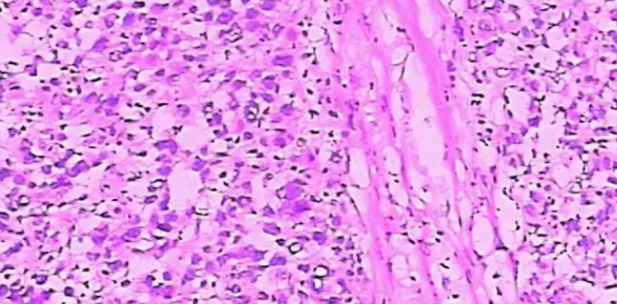

浸润性癌:80%的乳腺癌都是浸润性癌,其中大部分是非特殊类型。特殊类型的浸润性癌有粘液癌、小管癌等。

原位癌:主要包含导管内癌、Paget's病(又称湿疹样癌)等。这类患者治疗效果最好,绝大部分不需要化疗,理论上复发转移率极低。